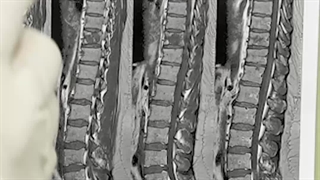

آناتومی ستون فقرات گردن و مشکلات آن